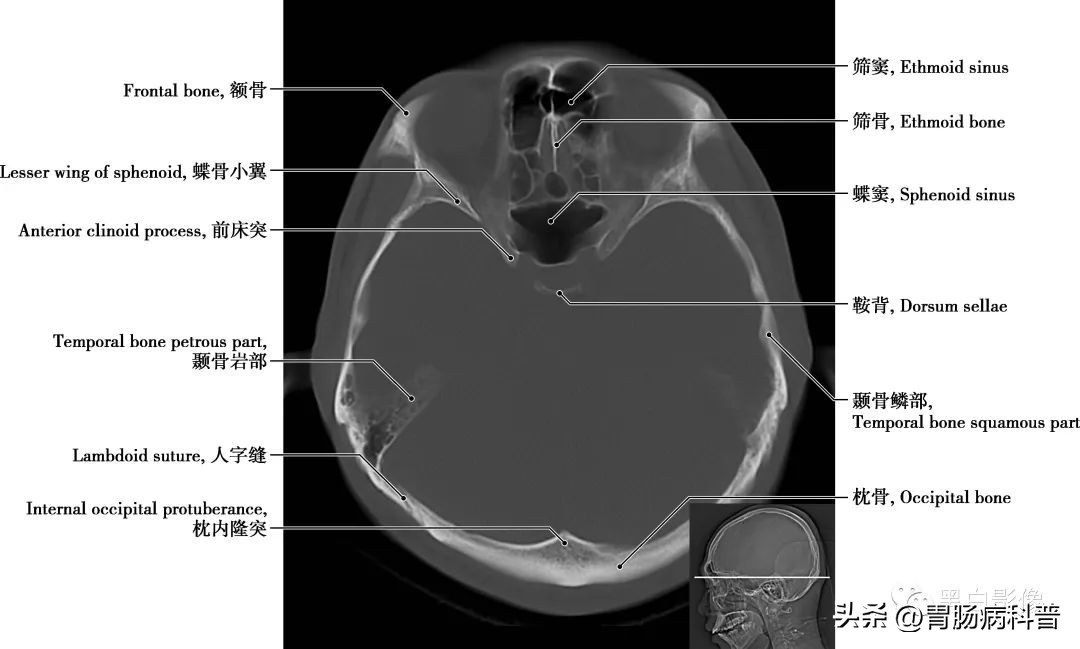

图1-2-13 经海绵窦轴位切面

蝶骨大翼 由蝶骨体部平伸向两侧,继而上翘,可分三个面,脑面位于颅中窝,眶面朝向眶,颞面向外向下。在蝶骨大翼近根部处由前向后可见圆孔,卵圆孔和棘孔,从棘孔入颅的脑膜中动脉在骨面上留有动脉沟。其后缘是颅后窝和颅中窝的分界线